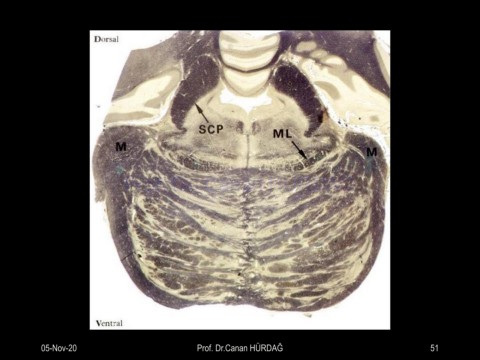

Page 51 - Merkezi sinir sistemi histoloji-2020

Prof. Dr. Canan HURDAG